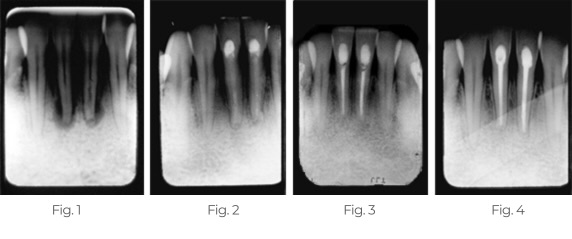

Tratamento da lesão periapical e da reabsorção interna

O doente apresentava um desconforto considerável e uma sensibilidade extrema ao calor, ao frio e à percussão.

Fig. 1: A radiografia de diagnóstico mostra reabsorção interna e lesão periapical da lateral esquerda do maxilar. O TEMPCANAL™ foi colocado nesta consulta (não mostrado).

Fig. 2: Radiografia tirada 3 meses depois mostra o TempCanal no lugar e a cicatrização periapical a ocorrer.

Fig. 3: Radiografia tirada após 13 meses mostra o canal radicular obturado com o Pulpdent Root Canal Sealer utilizando a Pulpdent Pressure Syringe®. Nota a ligeira extrusão do cimento para além do ápice e o espaço de reabsorção interna obturado com cimento.

Fig. 4: Radiografia tirada após 19 meses mostra a reabsorção interna controlada e a lesão periapical cicatrizada. Nota a lâmina dura. Mostra também uma parte do Root Canal Sealer removido e todo o dente reforçado com a restauração de compósito Pulpdent® HardCord dual cure, utilizando DenTASTIC® como adesivo de ligação.